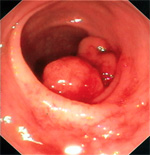

Los Pólipos son lesiones que al revés de los divertículos, protuyen hacia la luz del colon, se dividen en pólipos hiperplásicos (benignos), pólipos hamartomatosos (Síndrome de Peutz-Jeghers) y pólipos neoplásicos (Pólipos y Poliposis colónica adenomatosa familiar) con capacidad de degeneración maligna. El diagnóstico se efectúa por colonoscopia y biopsia, siendo la polipectomía endoscópica el auténtico tratamiento preventivo. - Diagnóstico y tratamiento de la litiasis biliar